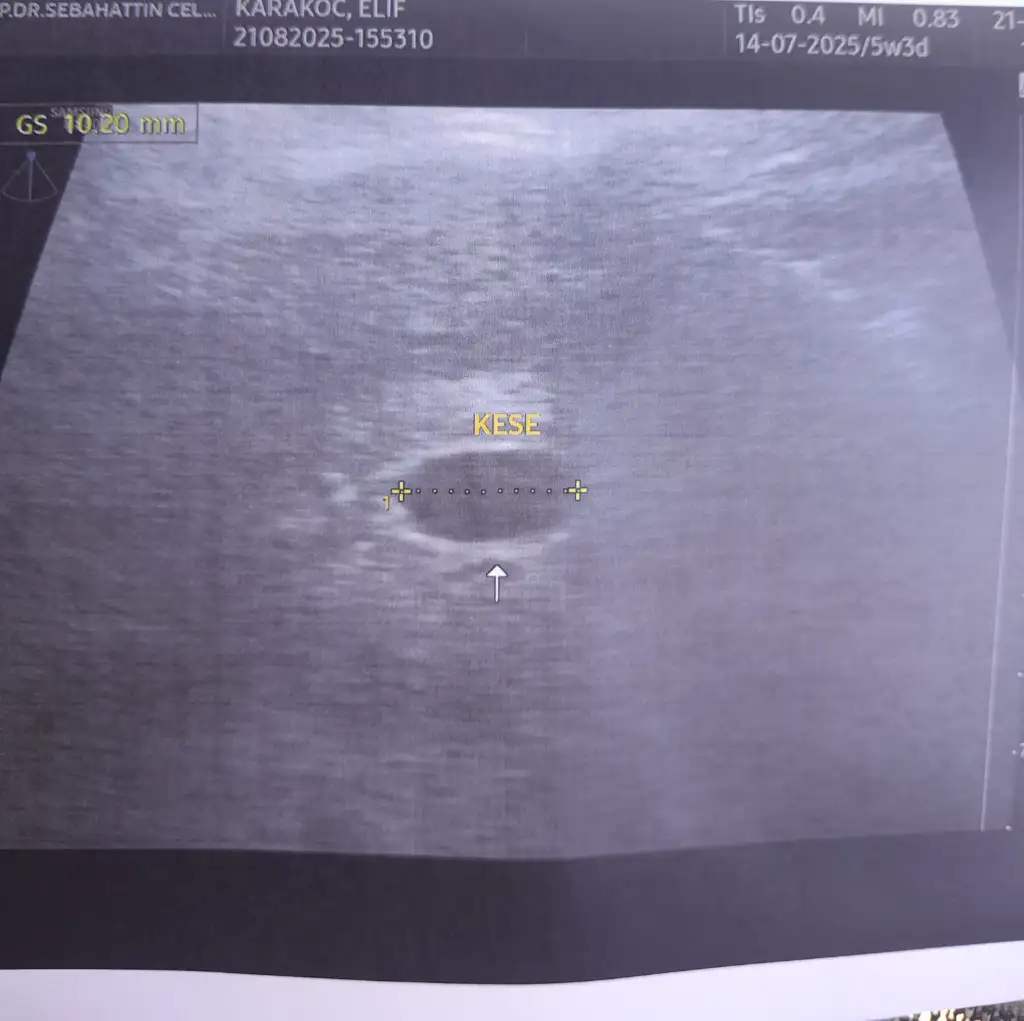

Benimde 5+4 kesem senin gibi yolk için haftaya cuma gidicem alttan bakmadiKızlar 5+3 günlük gebeyim tüp bebek ile oldu. Karından muayene etti bakabilir misiniz normal mi gününe göre. Yolk için erken alttan muayene ye gerek yok 10 gün sonra gel zaten bekleyeceksin dedi.

Merhaba içinizi ferah tutun sağlıklı bebek ne olursa tutunuyor arkadaşımın kanaması kanama alanları vardı çok fazla,doktor düşük yapıyorsun dedi eve git düşmezse pazartesi kürtaj olacaksın dedi. Ama bebiş şu an 7 aylıkKesenin şekli düzgün değil dedi kanama alanı varmış progestana devam dedi çok olumlu konuşmadı sadece bebeği gördü